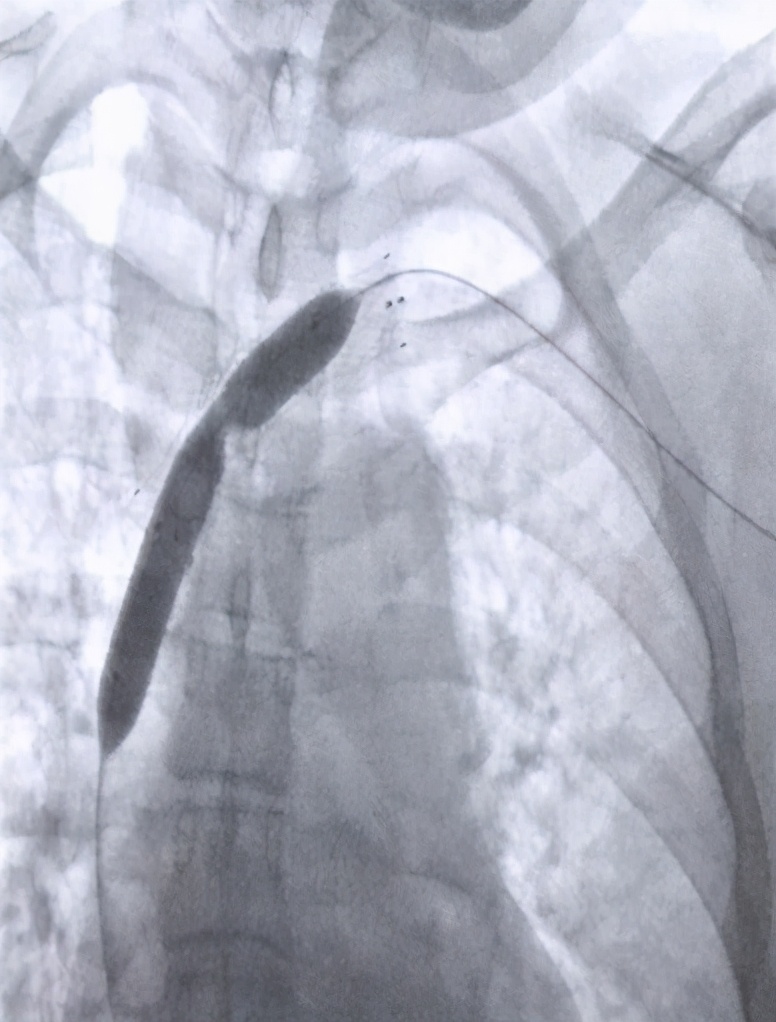

急性胸背部疼痛:急性胸背部疼痛可能为夹层导致,发病突然,危险度高,病变常迅速向近端扩展导致心包填塞而致患者死亡,或向远端延伸阻塞主动脉的分支血管出现相应部位缺血,其中Stanford A型主动脉夹层24小时死亡率>35%,超过一半的患者在48小时内死亡,30天死亡率>95%。因此,尽早处理,选择合适的治疗方式是挽救生命的关键。TAAD单一的内科保守治疗效果不好,一经确诊,应积极手术治疗。

当您胸痛由肩背-胸背-腰腹-下肢转变时,且合并胸片纵膈增宽+化验检查D-二聚体升高,建议尽早血管外科就诊,急诊完善胸主动脉CTA。明确是否存在主动脉夹层。